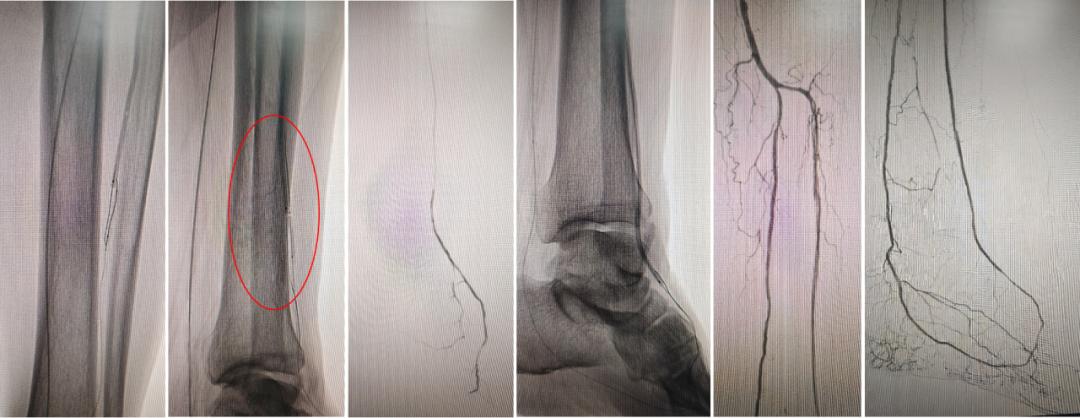

Case 1:胫前动脉长段闭塞,导丝成袢后通过,IVUS显示大部分位于假腔,但血流仍可维持。

Case 2:类似病变,成袢后导丝全程位于真腔,仅局部转弯处有夹层形成。

★ 经足弓逆向开通胫前动脉

Case 3:一例腘动脉闭塞患者,胫前动脉远端不显影,足底动脉仅通过侧支隐约可见。术者选择顺穿足底动脉,导丝经足弓上行,成功进入胫前动脉真腔,建立轨道后完成球囊扩张,恢复足弓血流,术后1个月患者溃疡愈合。